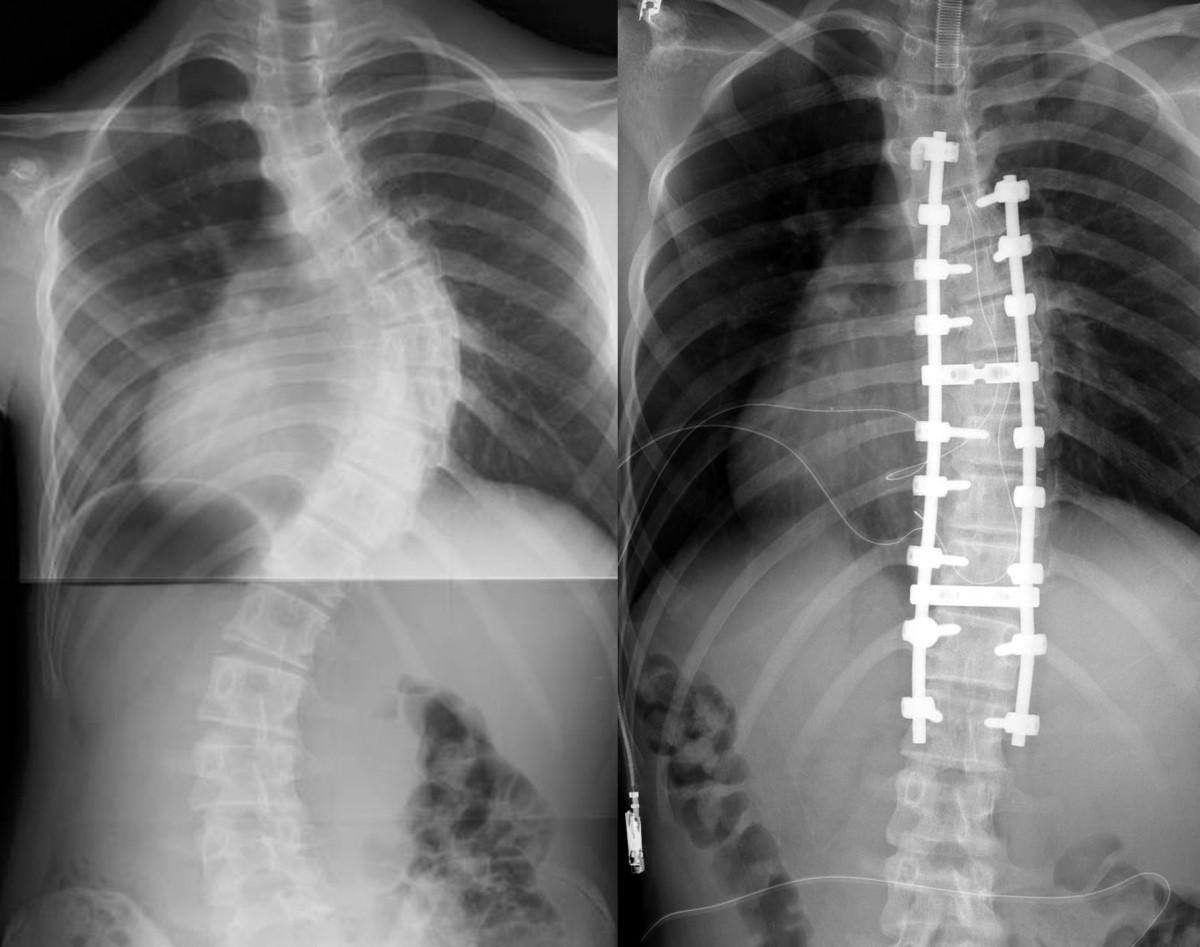

Surgery to correct scoliosis involves placing one or two metal rods stabilized by hooks and screws along the spine in an effort to prevent further curvature. Posterior fusion with instrumentation has been a standard of the surgical treatment for scoliosis since first introduced by paul harrington. The traditional way to treat scoliosis involves periods of observation, bracing (though this is generally for adolescent patients whose spines are not fully developed) and then surgery if the curve progresses much past 40 degrees.

Posterior fusion with instrumentation has been a standard of the surgical treatment for scoliosis since first introduced by paul harrington. The standard surgical treatment for scoliosis is a spinal fusion that corrects spinal deformity curves. With any of the surgical options, maximizing nutrition and medical status prior to surgery are critical to minimize complications.

When the angle exceeds 45 to 50 degrees, surgical correction may be necessary. This procedure fuses together vertebrae to stop progression of scoliotic curves. The purpose of the surgery is to fuse the curved vertebrae of the spine into one large bone.